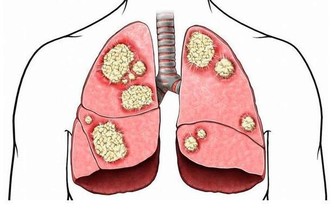

2、免疫力低下

有些人唇皰疹的發病率可能為一年兩次,而有的人可能每個月都會有唇皰疹的症狀。而反復發作的病人是終身攜帶病毒,病毒已經躲到神經結裡面了,當人處於比較疲勞的狀態,抵抗力下降,病毒又會活躍而發病,所以,這類患者則屬於復發性單純皰疹。

當你出現嘴邊長泡,或者口腔潰瘍、感冒、鼻炎等問題,並且都是經常反复,老不好時就要留心免疫力的問題了。